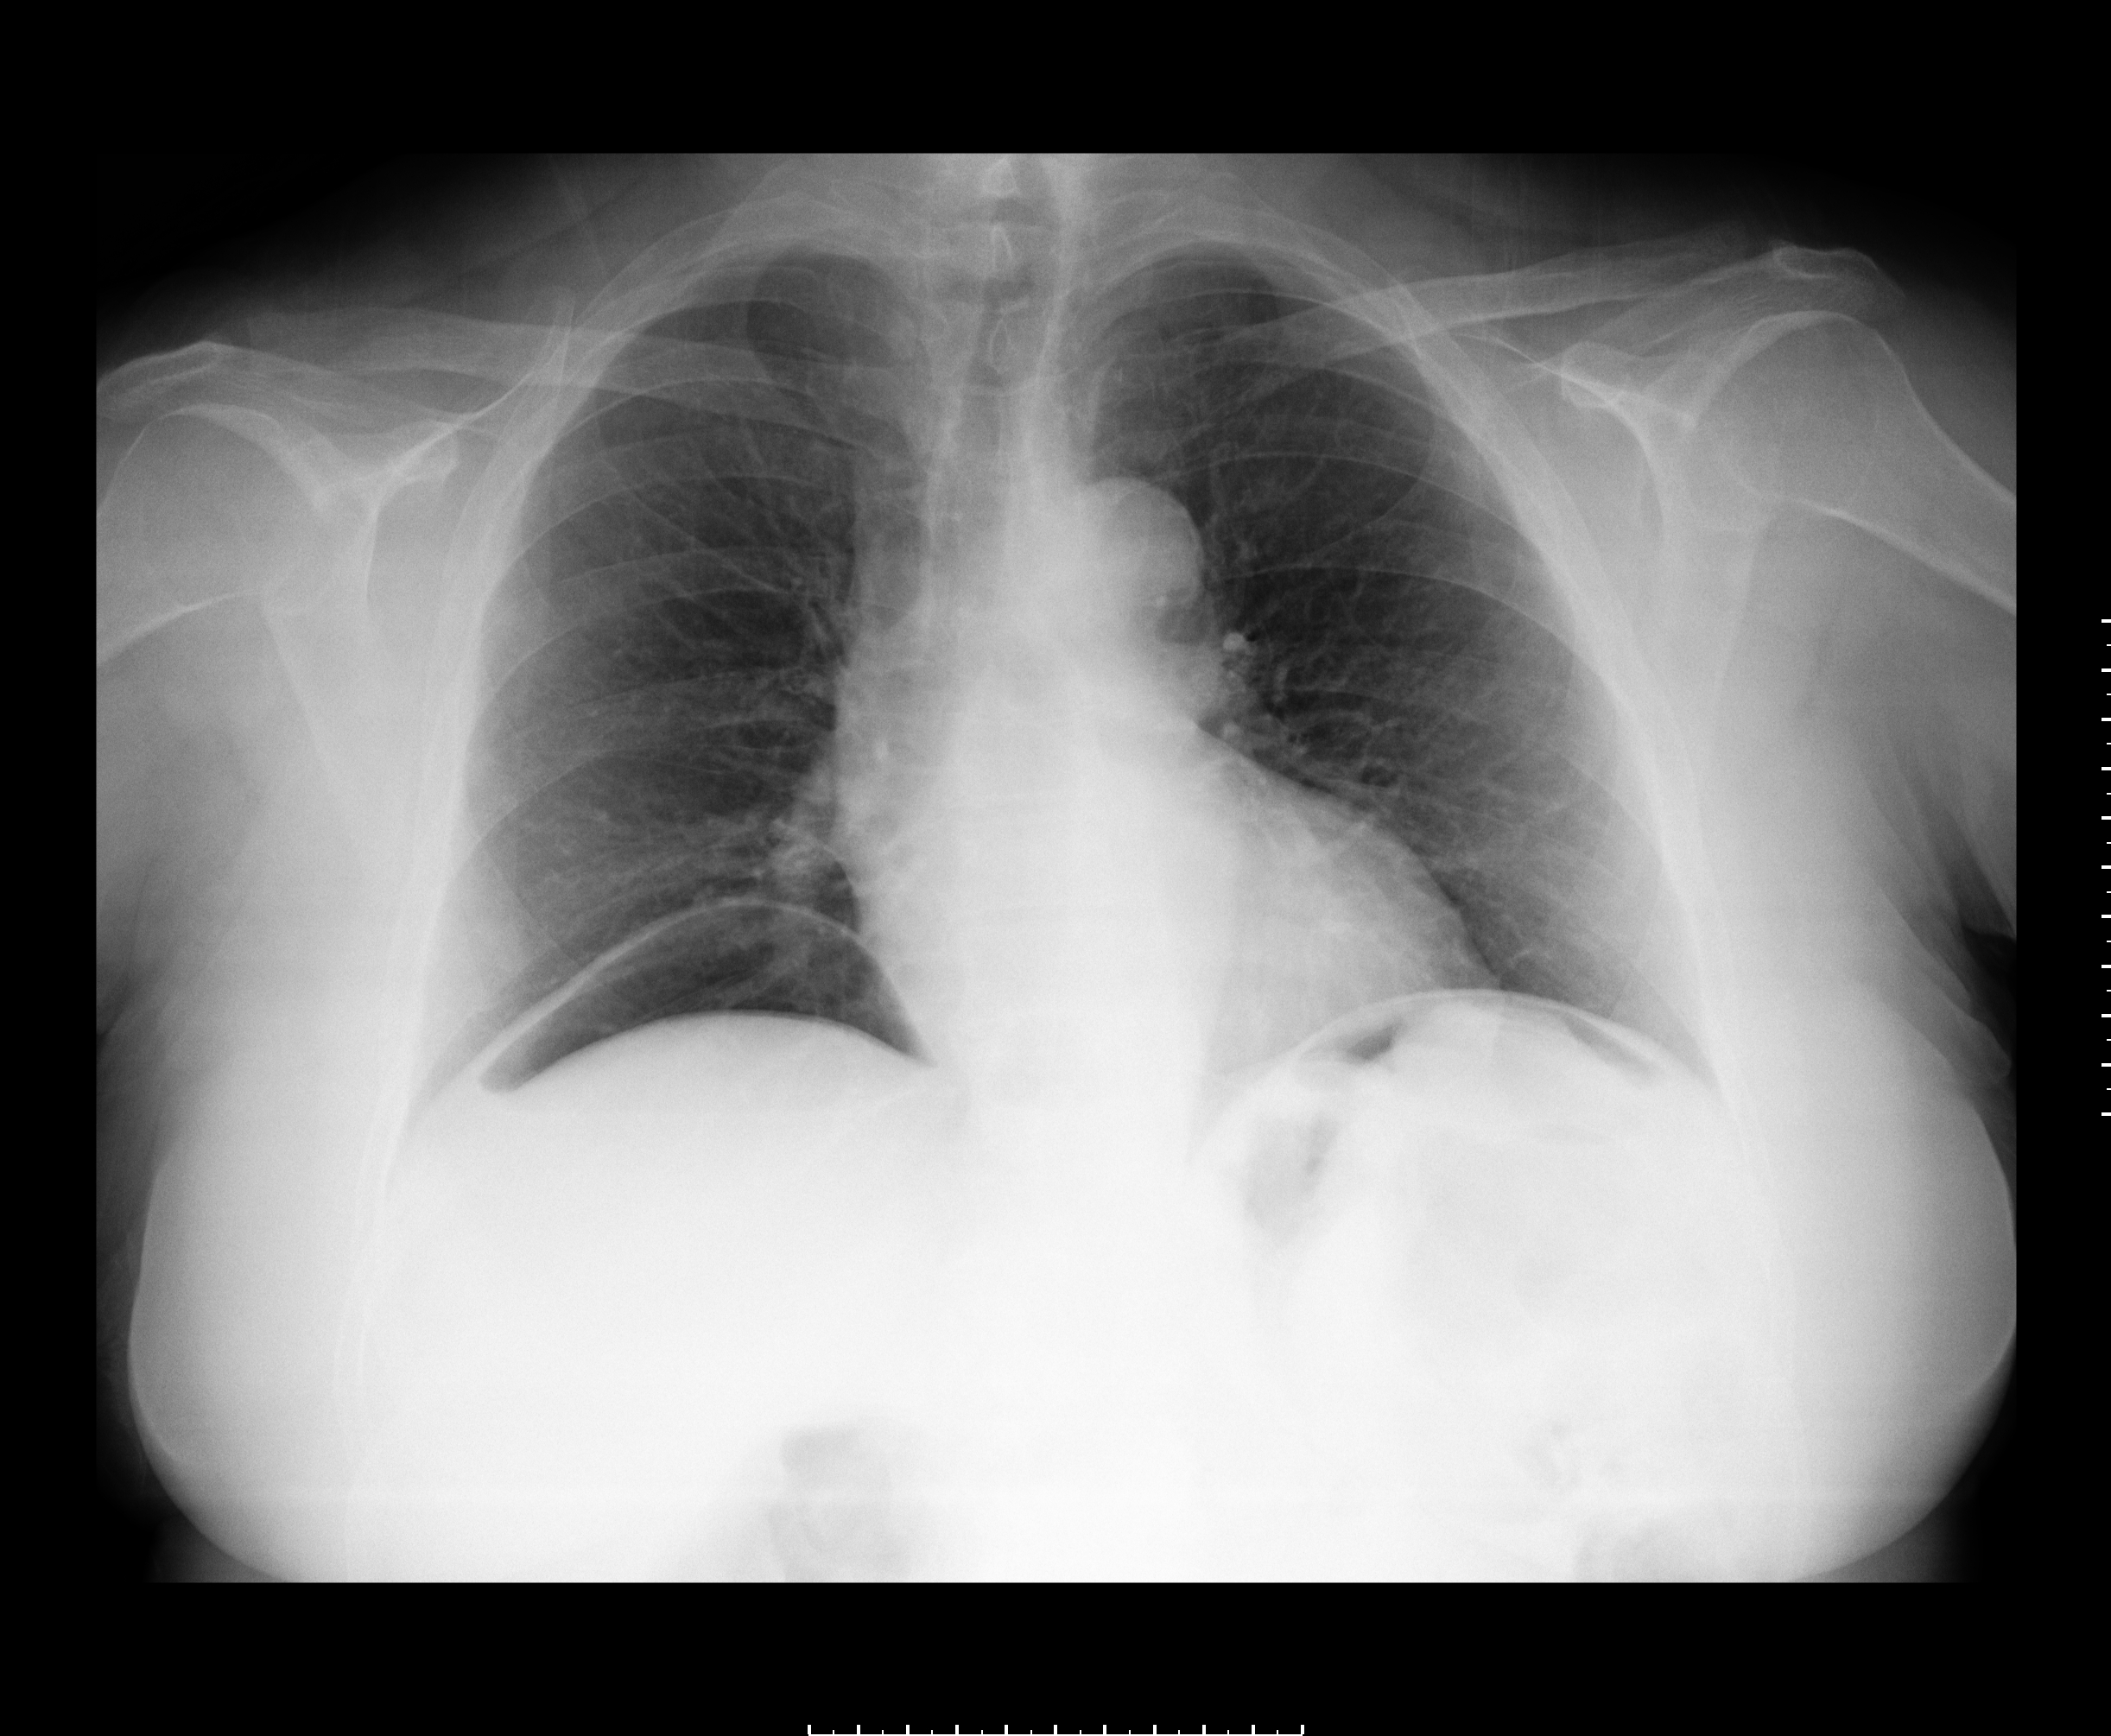

Pneumoperitoneum (PP) in peritoneal dialysis (PD) patients is a rare complication; however it should be considered to avoid an unnecessary laparotomy and that will also compromise the dialytic options. A 70 year-old woman with end-stage renal disease had been on chronic PD with automated night therapy for 21 months, without complications or any signs of peritonitis. She was admitted with a sudden epigastric pain. Tympanic abdomen was present on physical examination. The Tenckhoff catheter exit site looked unremarkable. Laboratory testing showed a normal white cell count. An important PP was visible in chest and abdominal X-rays. Contrast-enhanced abdominal CT scan confirmed a generalised PP distributed in supramesocolic recesses. No extravasation of endoluminal contrast was seen. Dialysis catheter was placed at left lower quadrant. We performed the aspiration of PP using an aseptic technique in Trendelenburg position. Abdominal X-ray showed resolution of PP. In the following day she was asymptomatic but abdominal X-ray revealed a newly developed PP, thus we decided to remove the catheter with no recurrence of PP.Downloads